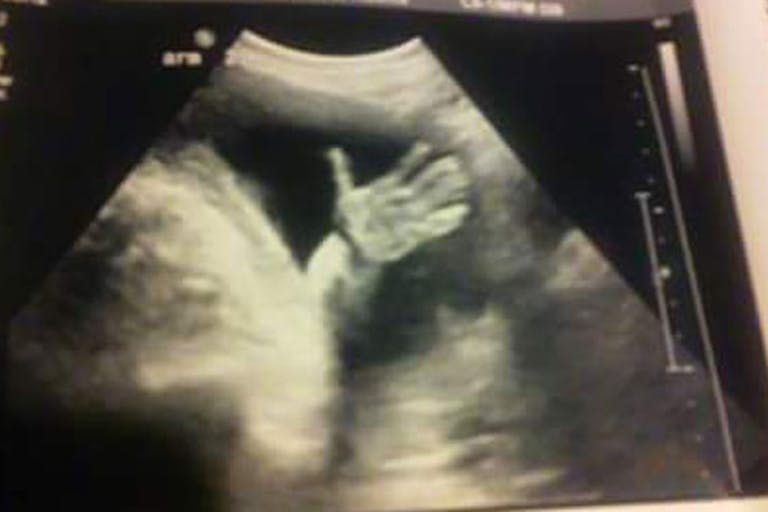

I laid back on a reclining leather chair, where the nurse gave me my ultrasound. We had no idea that I was already 18 weeks along. It was moving around and waving its hands! The nurse said the baby looked totally healthy. Darren and I both started to cry.

We are so thankful that we chose to get an ultrasound in the Stork Bus. If we hadn’t, we might have never learned that our baby was actually completely healthy. We realized that we could not let the difficulties in our pasts define our future. We can’t wait to be a healthy family of three in a little over a month!